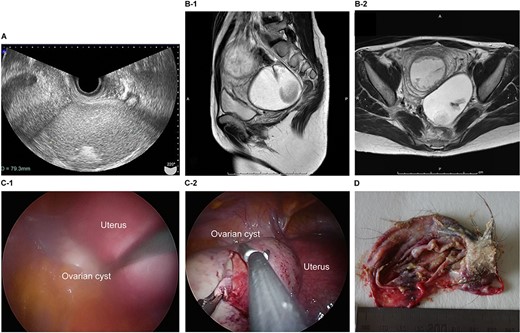

The patient was a 40-year-old, gravida 1, para 0 woman with no familial or medical history. She conceived naturally and was diagnosed with a left ovarian cyst at 5 weeks gestation by another doctor. She was referred to our hospital for further examination and operation. TVUS revealed a fetus in the uterus and a mass 6 cm in diameter on the left ovary, which appeared to be a dermoid cyst. MRI revealed left ovarian cystic tumors with fat tissue. The laboratory values, including the levels of tumor markers (e.g. CEA, CA-125, CA 19–9 and SCC) were within the normal limits. We performed single-port laparoscopic surgery at 17 weeks and 0 days gestation to remove the left ovarian cysts. The procedure was performed within 59 minutes, and there were no complications (Fig. 2).

Imaging studies and laparoscopic views and specimen photograph of case 2. (A) Transvaginal ultrasound image showing an ovarian cyst. (B-1) Sagittal T2-weighted magnetic resonance image (MRI) showing an ovarian cyst. (B-2) Axial T2-weighted MRI showing an ovarian cyst. (C-1) Gestational uterus: ovarian cyst was moved from the pouch of Douglas. (C-2) Ovarian cyst was moved and located on the gestational uterus. (D) Ovarian Cyst.